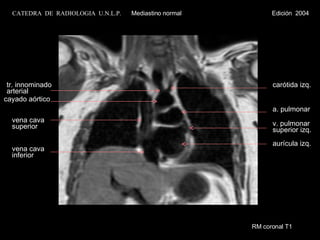

RM coronal T1 vena cava inferior vena cava superior cayado aórtico carótida izq. tr. innominado  arterial aurícula izq. v. pulmonar  superior izq. a. pulmonar CATEDRA  DE  RADIOLOGIA  U.N.L.P.   Mediastino normal  Edición  2004

RM coronal T1vena cava inferior vena cava superior cayado aórtico carótida izq. tr. innominado arterial aurícula izq. v. pulmonar superior izq. a. pulmonar CATEDRA DE RADIOLOGIA U.N.L.P. Mediastino normal Edición 2004